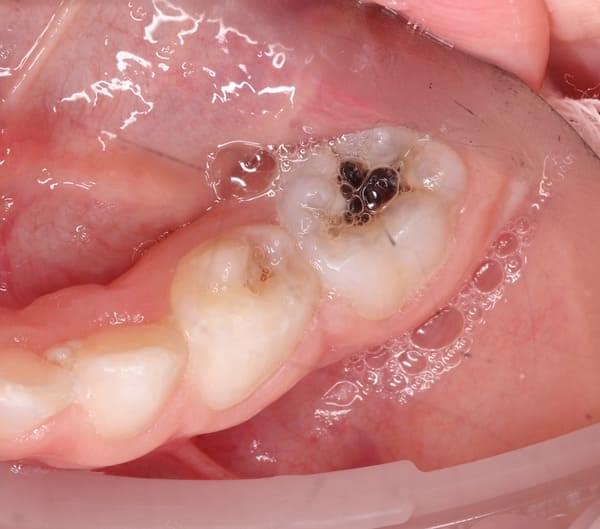

Система кореневих каналів молочних зубів часто складніша, ніж у постійних. Тому ми використовуємо ізоляцію робочого поля за допомогою кофердаму та спеціальне обладнання, щоб гарантувати високу якість лікування.

Важливо розуміти: це не швидка процедура. Вона вимагає ретельного очищення, промивання та пломбування каналів спеціальними матеріалами. Поспіх у цій справі може призвести до серйозних ускладнень у майбутньому.